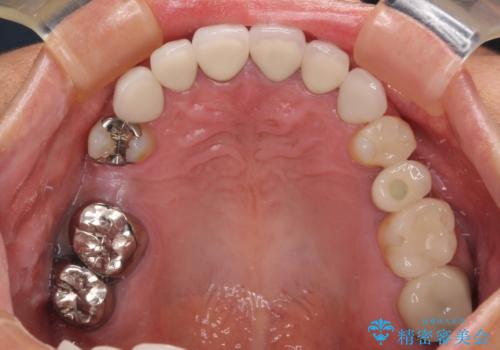

- 地元の歯科医院で治療を行っていたものの、難しいので都会に行くように指示をされたとのことで来院された患者様です。

右下のむし歯が歯肉縁下に及んでおり、歯周外科処置(歯冠長延長術)を行った上で、根管治療を行い、状態を整えて補綴治療を行うこととしました。

上顎前歯の根尖病変に痛みがありましたが、既に前歯が補綴治療済みであっため、外科的歯内療法(歯根端切除術)を行うことで解決することとしました。